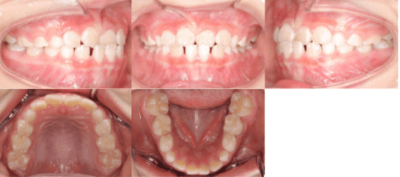

<治療前>

初診時は7歳2ヶ月で、前歯のかみ合わせが反対になっていることが主訴で来院されました。前歯部の反対咬合の診断により、「インビザライン・ファースト」を使用して治療を開始しました。

治療期間は6ヶ月で、下顎の前歯が上顎の前歯より前に出ている「交叉咬合」が改善されました。

治療のリスクとしては、矯正治療時に歯が移動する際に生じる痛み、歯根の吸収、むし歯が挙げられます。治療費用はおよそ40万円です。